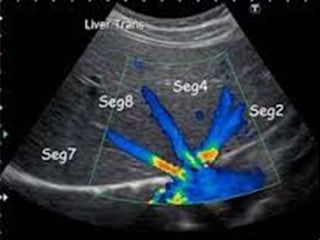

 SEGMENTACIÓN HEPÁTICA

 Para segmentar el hígado:

 SHD: el LHD en anterior y posterior

 SHM: lóbulo hepático derecho e izquierdo

 SHI: LHI en medial y lateral

2.- Suprahepáticas